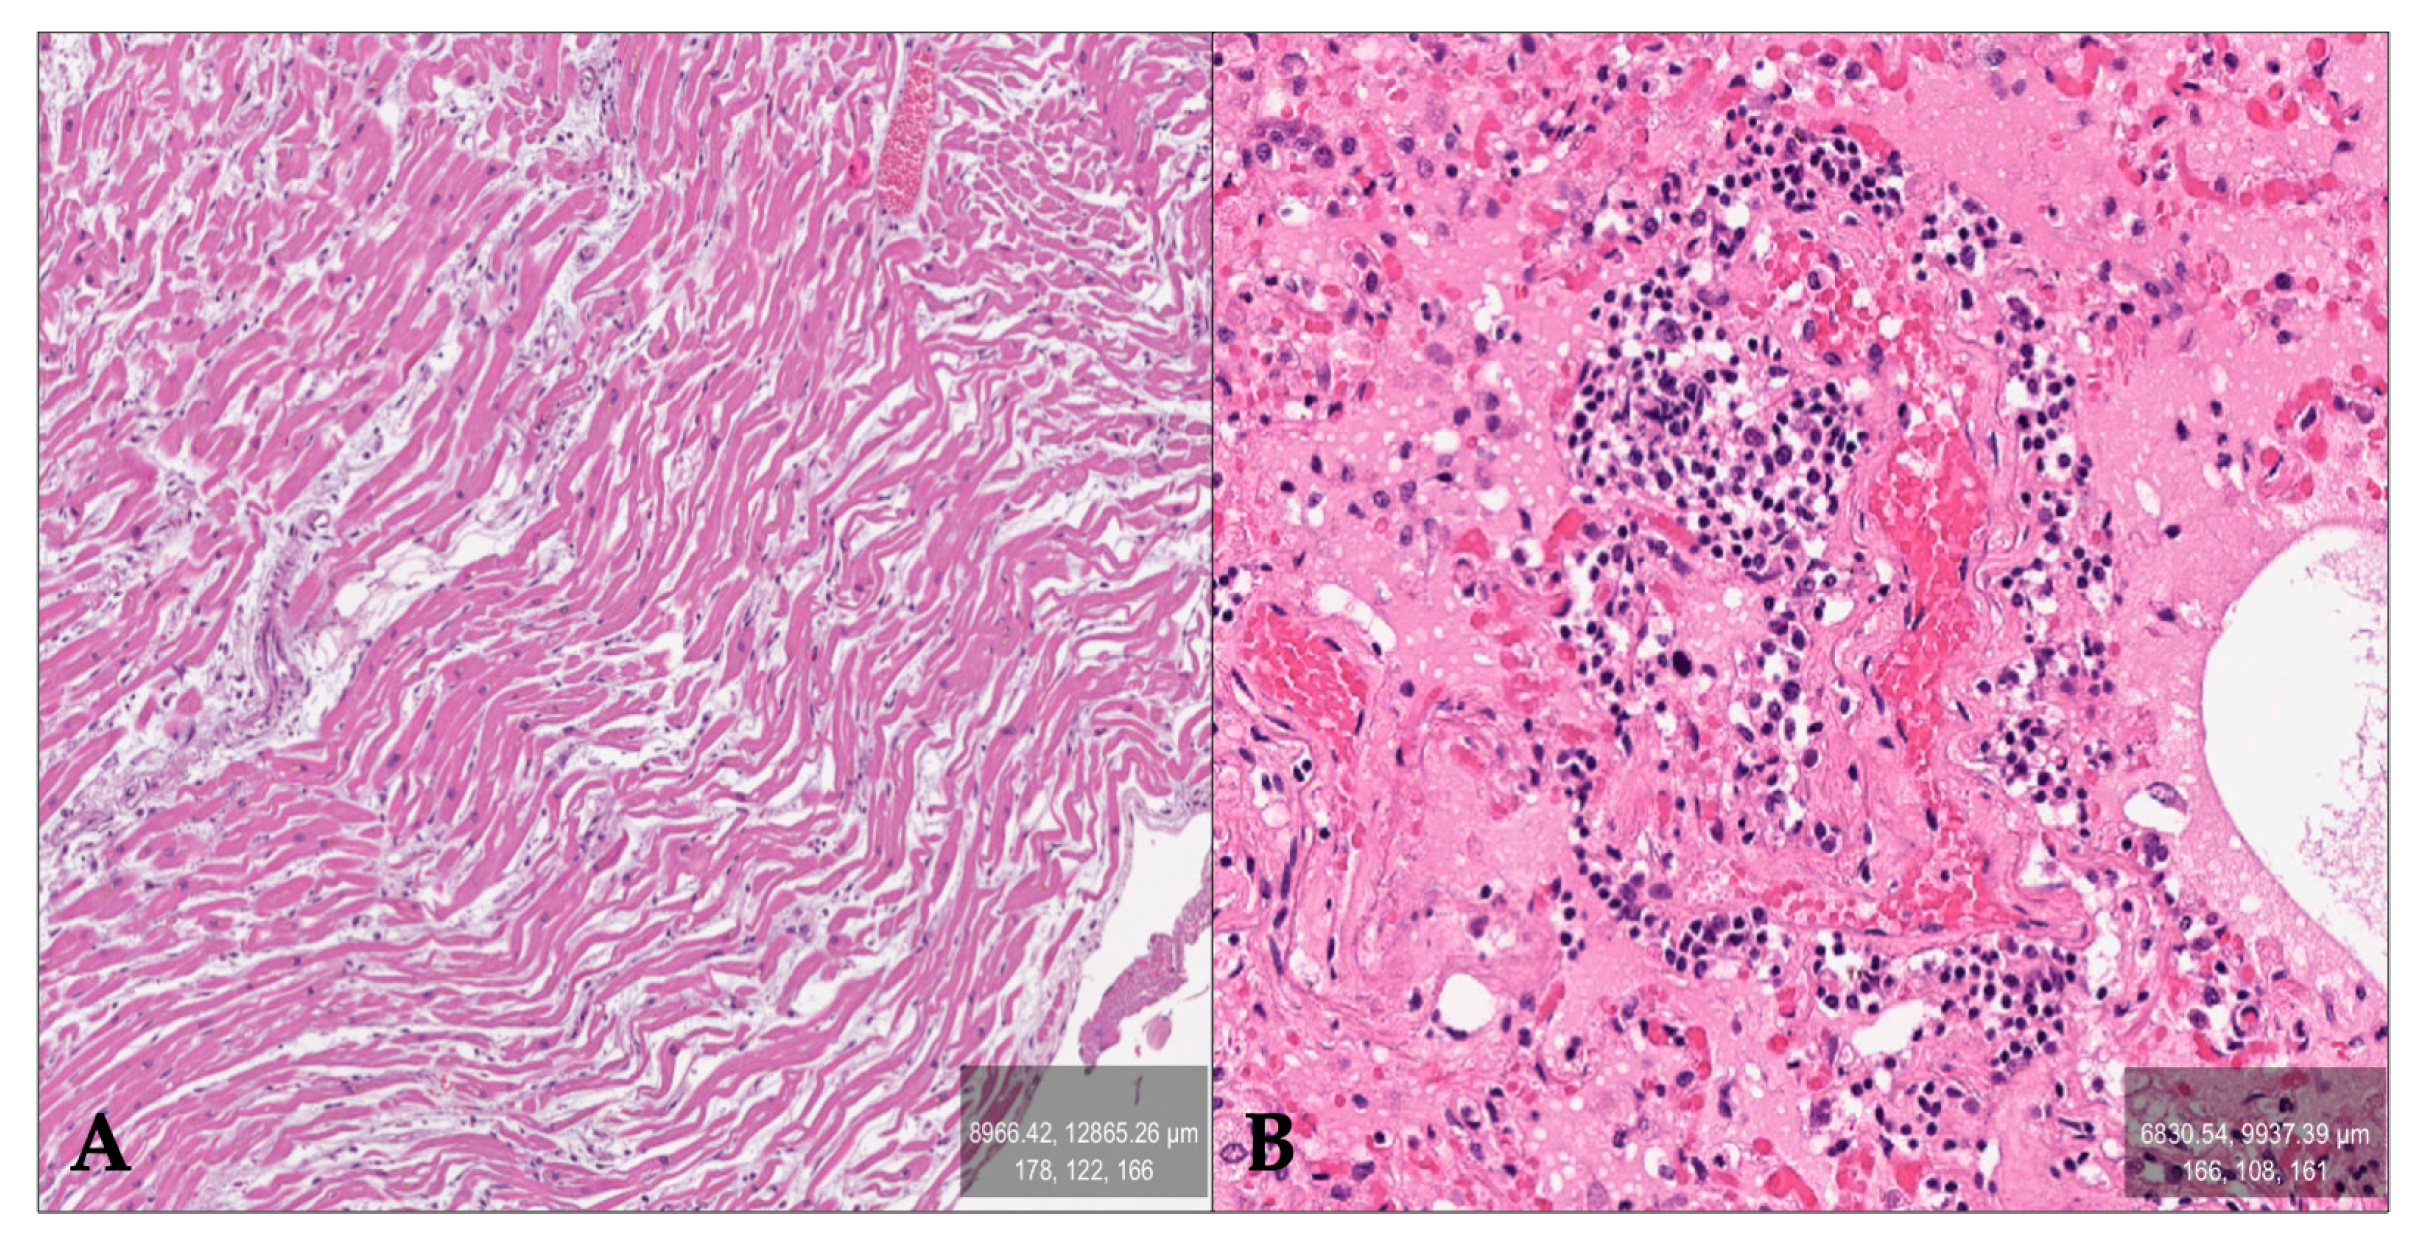

Histological examination was performed using hematoxylin and eosin staining. Wavy bundles of myofibrils and coronary arteries with atheromatous plaques in the heart were detected (caliber reduction varying from 40% to 30%) (Figure 1A); lymphocytic and granulocytic infiltrate in the walls of small- and medium-caliber vessels, along with patchy deposition of perivascular histiocytic-macrophagic elements in the lungs (Figure 1B); liver parenchyma displaying mild microvesicular steatosis (5%); preservation of the cortico-medullary pattern with minimal signs of inflammation in the kidneys; and the spleen exhibited extensive hyperplasia of the white pulp. The brain and cerebellum showed no remarkable histological findings. PTAH staining was also performed to investigate the presence of thrombi in the vessels, yielding inconclusive results. Detailed immunophenotyping was performed by a skilled pathologist to typify the lymphocytic and granulocytic infiltrates in the lungs. The results showed the prevalence of T-CD3+ and CD15+ elements, thus identifying small vessel vasculitis (Figure 2A,B). Subsequent immunophenotypic analysis using CD68 staining revealed punctate deposition of perivascular histiocyte–macrophage elements.

Figure 1. Findings on histological examinations: (A)—Heart: wavy fibers (H&E, 20×); (B)—Lung: intra-alveolar edematous stasis, perivascular leucocytic infiltrate (H&E, 40×).